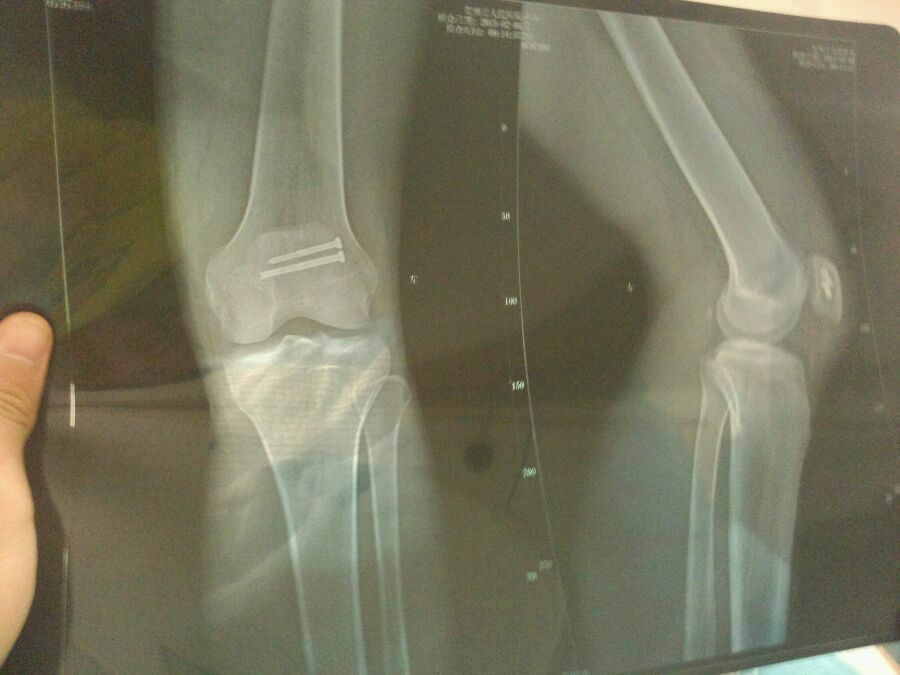

X光照片是术后第三天照的 现在弯这个角度是多少度 昨天刚刚拆的线

八十度了,髌骨早点活动好,就怕时间久了粘连。